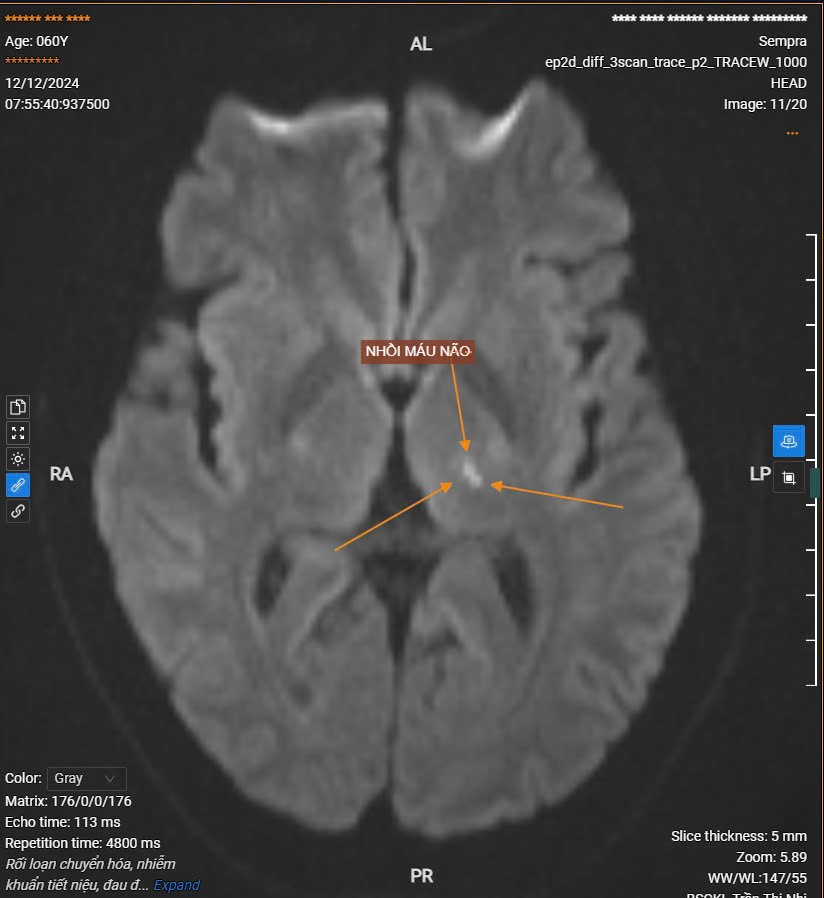

Dưới đây là một số hình ảnh chụp MRI sọ não cho bệnh nhân gặp các vấn đề: đau đầu, tê tay, tê môi, liệt nửa người, ... khi thăm khám tại BVTB trong những ngày qua.

Bn nam 60 tuổi đến khám vì đau đầu, tê môi kết quả chụp MRI sọ não phát hiện hình ảnh ổ nhổi máu nhỏ bán cấp sớm vùng đồi thị trái